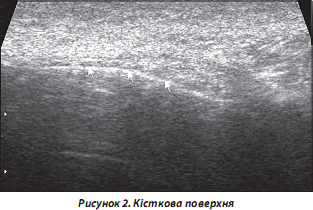

2. Кісткові структури. УЗД дозволяє отримати тільки зображення поверхні кістки у вигляді гіперехогенної лінії. Поздовжнє та поперечне сканування слід проводити перпендикулярно кістковій поверхні. При РЗС можлива візуалізація ураженого періосту у вигляді нечіткої гіперехогенної смуги (артрити, у тому числі РА, СпА, псевдоерозивний варіант ОА тощо) (рис. 2).